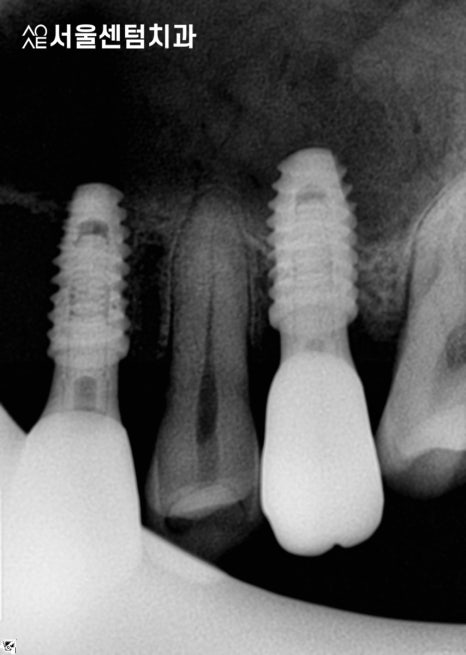

앞니임플란트 완료

각 부위별로 잇몸치료를 진행 후

어금니쪽 보철물을 먼저 수복하였습니다.

앞니는 제일 마지막에 제작하였고요.

기간 차이는 있었지만

전부 성공적으로 마무리되었습니다.

이 분은 특히 어려운 수술인

상악동거상술도 함께 진행하였고

앞니여서 심미성도 신경써야했습니다.

성공적인 앞니임플란트 결과

기간은 총 4개월 조금 넘게 걸렸습니다.